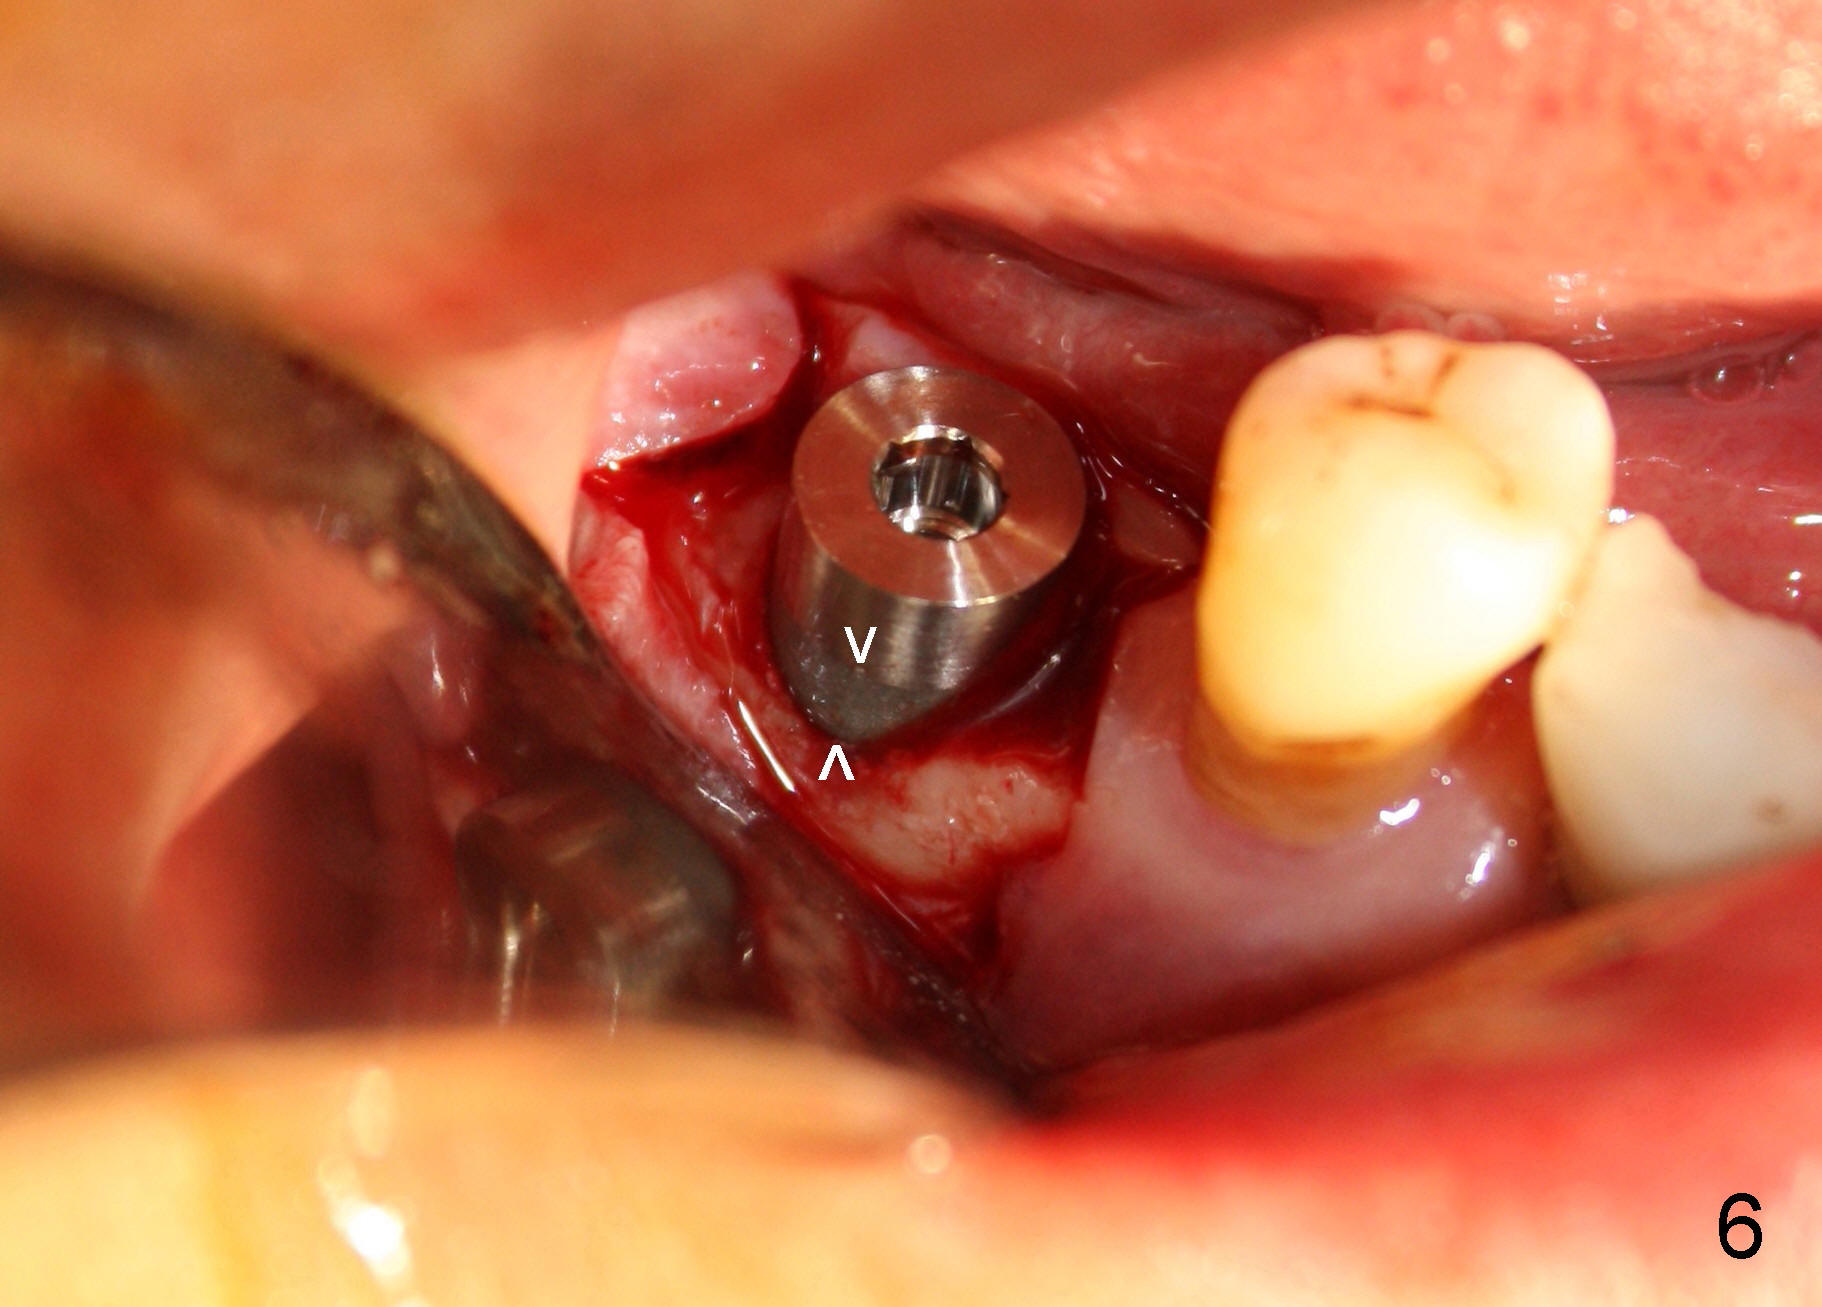

CBCT studies show that a 6x11 mm implant can be safely placed at the site of the tooth #30 (Fig.1 (coronal), 2 (sagittal section). Osteotomy is initiated by 2 mm pilot drill at the depth of 8 mm from the crest (the prospective implant is 3 mm above the crest); X-ray is taken with a parallel pin (Fig.3 P). It appears that there is 12 mm of bone from the crest to the upper border of the inferior alveolar nerve canal. The depth of osteotomy is accordingly adjusted to 11 mm below the crest; osteotomy finishes with insertion of 6x14 mm tap (Fig.4); the patient feels pressure while the tap is being inserted. Following further infiltration with Lidocaine, the depth of the osteotomy is intended to increase in order to bury the implant deeper, because the coronal portion of the buccal plate starts to perforate. The patient feels pain. Finally a 6x14 mm implant is placed ~ 1 mm above the inferior alveolar canal (Fig.5). As mentioned earlier, the rough surface of the implant is exposed buccally (Fig.6 between arrowheads). The nearby buccal plate is decorticated (Fig.7). The autogenous bone harvested during osteotomy (Fig.8) is going to be placed over the exposed portion of the rough surface of the implant (Fig.9); the graft is covered by collagen dressing (Fig.10). The buccal and lingual flaps are approximated with sutures mesial and distal to the implant (Fig.11). To increase the retention of perio dressing, a 4x3 mm abutment is placed.